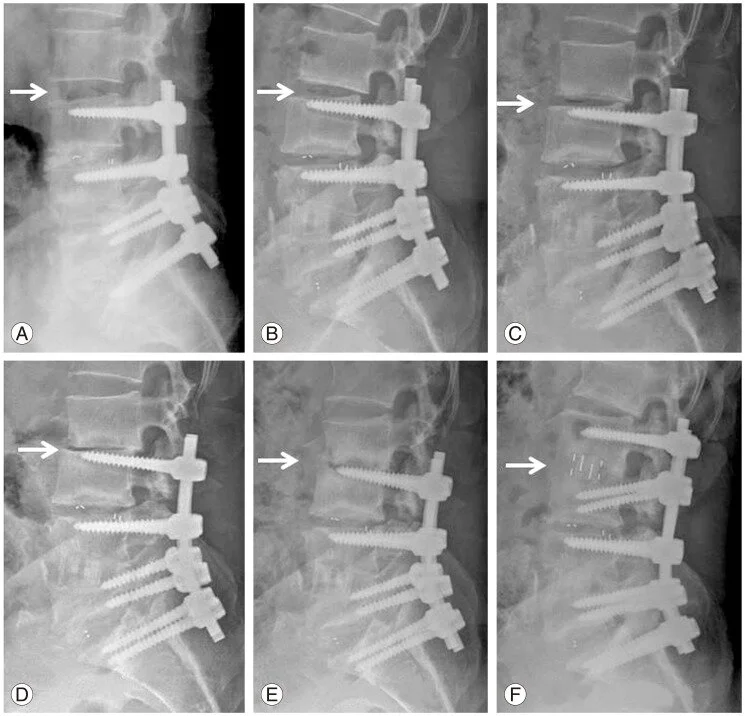

• The spine fusion forever changes the biomechanics of the back and is thought to increase the stress placed on the other (non-fused) joints in the lower spine. This leads to accelerated degeneration of the adjacent levels of the spine, including instability. In one study, more than one-third of patients required surgery at an adjacent level by 10 years.

A, B, C, D, E show progressive fastened degeneration of the adjacent disc space above the fusion surgery, until it also eventually needed fusion in F. https://www.ncbi.nlm.nih.gov/pmc/articles/PMC4591457/